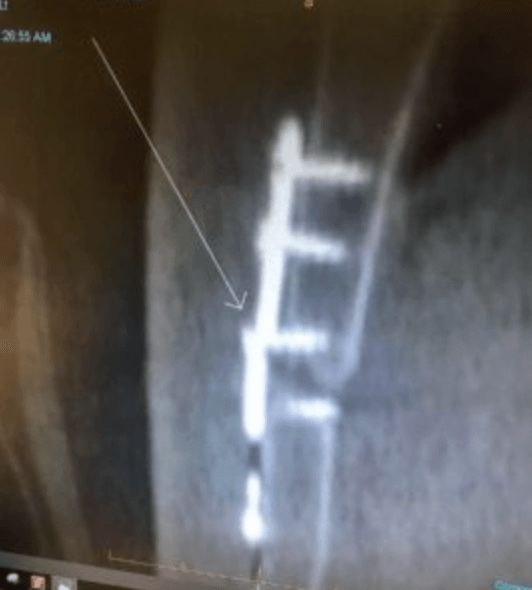

Multiple World Champion BMX athlete and Olympic hopeful, Caroline Buchanan has gone through hell and back this past year after testing injuries and falls that resulted in eight medical procedures in 2018 alone. These setbacks have cost her on the track but have also taken a huge toll on her financially.

Caroline’s injuries and subsequent surgeries have been well documented as well as her rehabilitation efforts to get her back on the bike. Unfortunately, one item not chronicalized has been the mounting medical expenses due to the multiple surgeries and one more surgery scheduled in the next few months.

Being the extremely talented and dedicated athlete that she is, Caroline has accepted this challenge head on and is determined to get back to what she loves most, racing. Road 2 Recovery has set up an R2R Fund for her and is working with medical billing to get these costs down to a manageable level. However, the bills are coming in at over $100,000, and Caroline needs all the help we can give. If you are able, you can make a tax free donation to Caroline’s R2R Fund here.